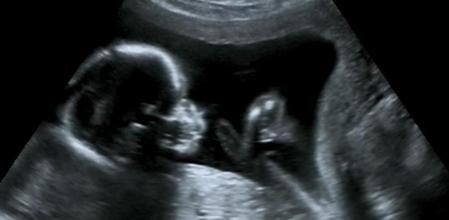

Diagnóstico por imagen

La difalia se detecta durante la gestación a través de métodos de diagnóstico por imagen.